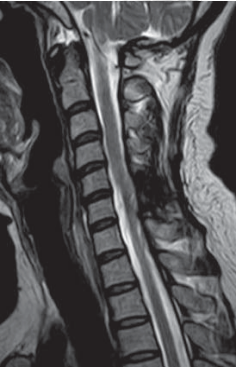

Imaging Studies

MRI with contrast of her cervical spine showed an intramedullary lesion at C6 level. It was a mass lesion that expanded the spinal cord. The enhancing nature as well the presence of a cyst at the upper end of the mass pointed to the likely hood of this being a ependymoma.